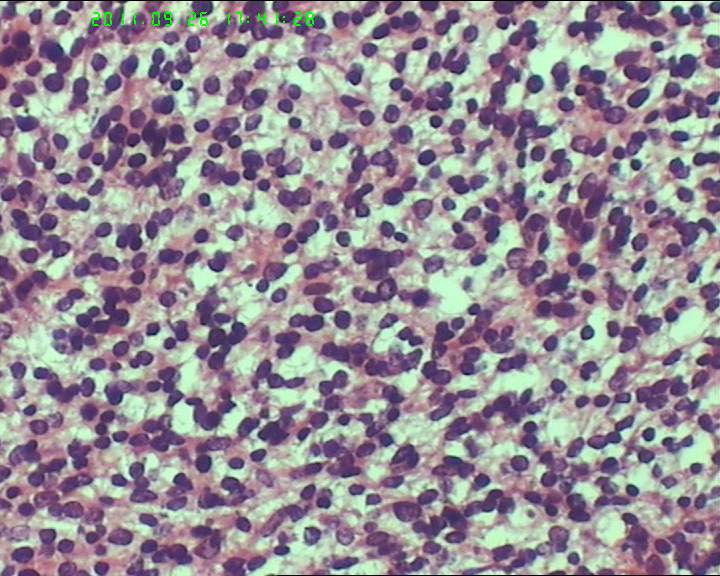

灰白不整形肿物一个,大小18*15*9cm,表面结节状,包膜完整,切面灰白,中央可见坏死区,质软,范围5*4cm。其余切面多彩 部分半透明状 质中。

鉴别诊断排排队:1、GIST,2、MPNST,3、去分化脂肪肉瘤,4、恶性间皮瘤,5、恶性SFT,6、平肉

主要考虑前二者。CD34,CD117,S-100,BCL-2,SMA, D2-40,CR, VIM. 结果如何?请楼主揭谜底吧。